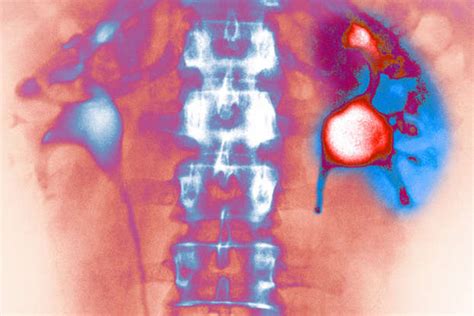

Let’s rewind a bit and talk about the absolute superstars of our internal filtering system: our kidneys. Seriously, guys, these organs are working 24 ⁄ 7 to keep us alive and well, and a massive part of that job is waste removal and filtration . Imagine your blood as a river carrying all sorts of things – nutrients, oxygen, hormones, but also metabolic byproducts, toxins, and excess salts. Your kidneys are the sophisticated water treatment plants that process this river. The kidney’s role in waste removal and filtration is nothing short of miraculous. Every single minute, your kidneys filter about a quarter of your total blood volume – that’s a lot of processing power! This filtering happens in tiny units called nephrons, and within each nephron, there’s a complex structure called the glomerulus. The glomerulus acts like a sieve, allowing small molecules like water, salts, glucose, and waste products (like urea) to pass through into the renal tubules, while keeping larger things like blood cells and big proteins in the bloodstream. As the filtered fluid travels through the tubules, the magic of selective reabsorption and secretion happens. Your body smartly reabsorbs the good stuff – like most of the water, essential salts, and glucose – back into the blood. At the same time, it actively secretes any remaining waste products and excess ions into the fluid. What’s left is urine, which then travels down to your bladder to be expelled from the body. This entire process is incredibly precise, ensuring that you get rid of harmful waste without losing essential nutrients or fluids. Now, think about what could go wrong. If the filtration barrier in the glomerulus gets damaged, larger molecules like proteins can leak into the urine (a sign of kidney disease). If the tubules can’t reabsorb water properly, you can become dehydrated. If waste products aren’t filtered out effectively, they build up in the blood, leading to toxic levels. This is where understanding the potential PSEglpse-1 effects on kidneys comes into play. If PSEglpse-1 is involved in maintaining the integrity of that glomerular filter, or in regulating the transport of substances across the tubular membranes, then any imbalance or dysfunction related to PSEglpse-1 could directly impair the kidney’s ability to perform these vital filtration and waste removal tasks. It highlights just how interconnected everything is within our bodies and why even a seemingly small protein could have significant repercussions on such a critical organ system. It’s truly mind-blowing!